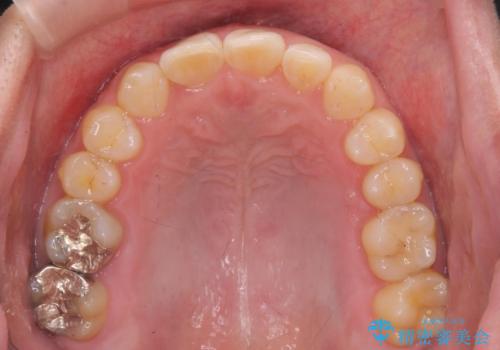

前歯のすき間 歯のがたつき

- 前歯のすき間とがたつきを主訴に来院。

右上の前歯は過去にがたつきがあったとのことで抜いてしまっていました。

歯の数を合わせるために、下の歯を1本抜いて矯正しています。

下の前歯を抜歯したことでブラックトライアングルができましたが、仕上げにIPRを加えることで目立たなくすることができました。